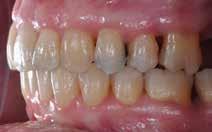

Patienttilfælde 1 (Fig. 1) er en 37-årig kvinde, henvist efter succesfuld behandling af stadie 3-parodontitis. Der er nu sundt

Før behandling

parodontium, ingen pocher over 4 mm, og både blødnings- og plakindeks er under 10 %. Patienten er motiveret for ortodontisk behandling, da hendes tænder er vandret over tid, delvist som følge af reduceret parodontium.

Der ses anterior trangstilling i begge kæber og overerupterede 1+1 og 2,1-1,2, hvilket resulterer i dybt bid med 2- tæt på ganepåbidning. Der er normale sidetandsrelationer, men der ses 5 mm horisontalt overbid (HOB) og 7 mm vertikalt

overbid (VOB). Papillen mellem 1+1 er betydeligt reduceret pga. fæstetab, og de mesialt kippede 1+1 har resulteret i en ”dark triangle”. Den facioorale funktion er for nuværende i.a. Panoramarøntgen (Fig. 1, I) viser marginalt knogletab i begge kæber og fravær af 8,7+7,8 og 8,7-8.

Objektivt anbefales behandling af det dybe bid, som ubehandlet forventes at forværres yderligere over tid. Patienten har ønske om behandling med æstetisk ortodontisk apparatur, alignere, og det vurderes muligt at behandle malokklusionen med alignere. Dog anbefales det generelt, at alignere undgås eller benyttes med væsentlige modifikationer af alignerens retention ved tandmobilitet, da dette ellers kan medføre jiggling, når aligneren tages af og på mange gange dagligt. På den anden side er der nogen evidens for, at alignerbehandling er associeret med bedre renhold og parodontal sundhed sammenlignet med fast apparatur (16).

Der planlægges alignerbehandling af begge kæber med intrusion af 1+1 og 2,1-1,2, nivellering af trangstilling UK med interproksimal reduktion (IPR) (Fig. 2 A, B) og senere IPR OK for reduktion af dark triangles mellem incisiverne efter nivellering. Patienten instrueres i at benytte alignere 20-22 timer/ dag med alignerskift hver 7. dag, og patienten ses hver 3.-8. uge under forløbet. Den første alignerserie består af 16 alignere for nivellering OK/UK og IPR i UK (Fig. 2). Efter denne serie planlægges IPR mellem incisiverne i OK for reduktion af dark triangles (Fig. 3) samt yderligere intrusion af OK og UK-fronten i 12 refinement-alignere. Patienten udviser god kooperation og er meget tilfreds med alignerapparaturet, som er mindre synligt end det faste apparatur (Fig. 4).

Behandlingen afsluttes med yderligere refinement-alignere for finindstilling af okklusionen, og efter 11 måneders ortodontisk behandling er der opnået normale relationer i alle tre